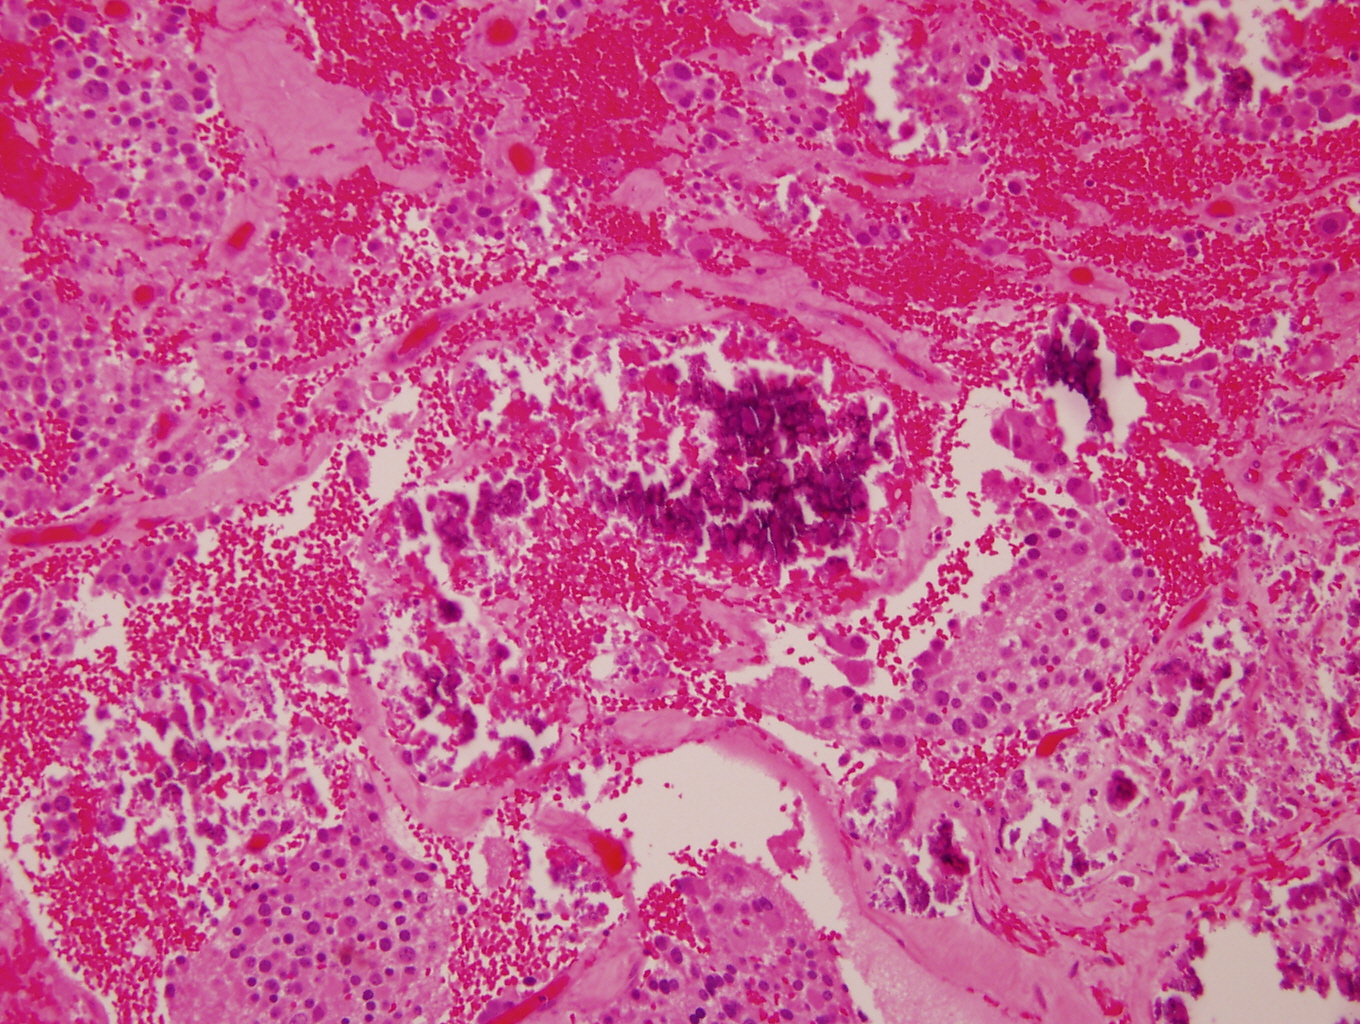

- Stroma rich, nodular subtype: area(s) of stroma poor, immature tumor are usually hemorrhagic with well defined borders (J Natl Cancer Inst 1984;73:405)

- May see neuromelanin pigment (brown, finely granular; rarely present), cystic degeneration, hemorrhage, dystrophic calcification

Nodular type